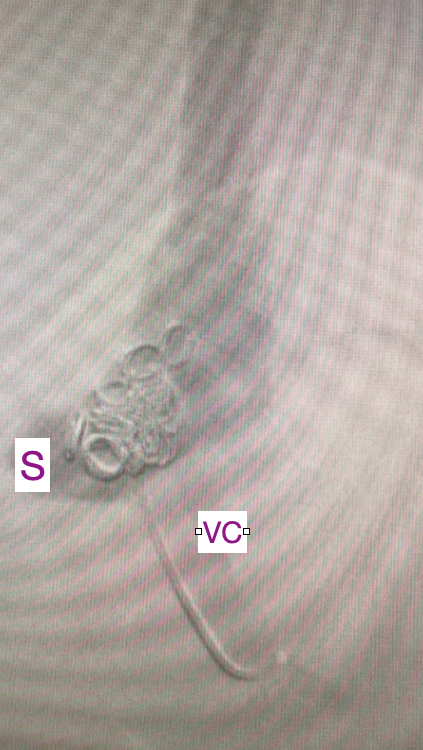

The Interventional Radiology (IR) team closing an abnormal blood vessel (S) in the liver of a dog draining into a large vein (VC). Multiple metal coils will close the vessel and return the dog's liver to normal! #weareAURA #portosystemicshunt @IRHorton @BSIR_News @IN_publishing